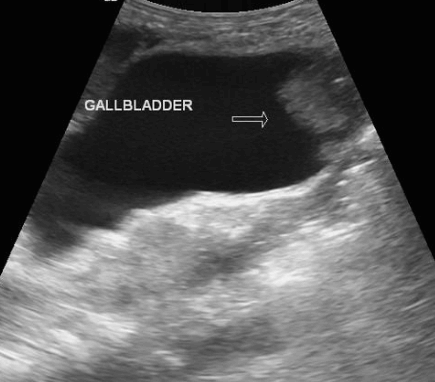

2. Wall thickening (벽비후형)

담낭벽이 국소적 또는 미만적으로 비후 된 암이며 점막하층이 없어 바로 간으로 직접 침윤하여 치사율이 높다. 담낭벽의 불규칙한 비후, 담낭 내강이 뚜렷하지 않으며 담낭벽을 나타내는 선상의 고에코가 뚜렷하지 않다.

벽비후형이 층이 없고, 내강 안 표면이 불규칙일 때, 비대칭적 비후, 담낭벽이 간을 침범할 때, 악성도가 높다.

GB wall thickening

1차성 질환 2차성 질환 Acute cholecystitis Liver cirrhosis Chronic cholecystitis Hepatitis Acalculous cholecystitis Ascites XanthoGranulomatous cholecystitis Renal failure GB cancer Pancreatitis Adenomyomatosis GB wall thickening 이 보일 때 감별 point